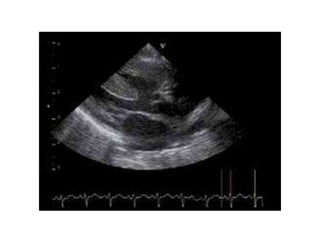

Echocardiographie

• PSGA : 3 critères diagnostiques sur 4 :

– CIV haute, large

– Aorte à cheval, dextroposée

– HVD

– Continuité mitro-aortique

• PSPA : voie droite ++ :

– Dimensions anneau, AP tronc et ses branches

– Gradient VD-AP : degré de sténose, avec parfois 2 flux

superposés

– Ostia coronaires

• Apicale :

– Fonctions ventriculaires

– CIV surajoutées

– Convergence des 2 flux ventriculaires vers l’aorte

• Sous-costale et supra-sternale :

– Diamètres branches AP

– Arteria lusoria (= sous-clavière Dte aberrante)